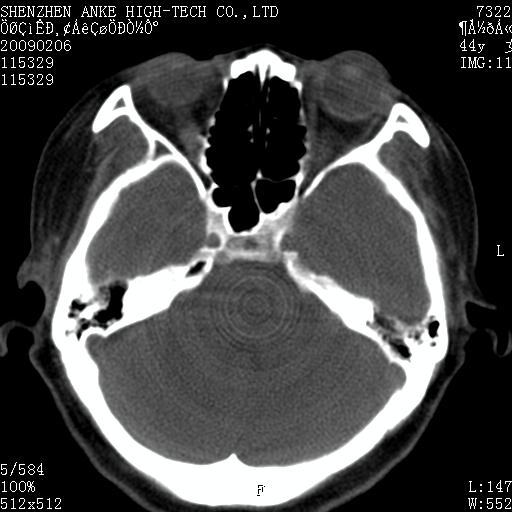

标题: CT17977:女,44岁,右侧颌部包块1年,右侧面瘫2月。 [打印本页]

患者:女,44岁,右侧颌部包块1年,右侧面瘫2月。

考虑右侧腮腺混合瘤可能性大

考虑右侧腮腺混合瘤。

考虑右侧腮腺混合瘤。年轮样伪影考虑机器问题!

右侧腮腺混合瘤可能性大

考虑右侧腮腺混合瘤;不排除腮腺癌。

右侧腮腺肿瘤,良恶性难定。

右侧腮腺混合瘤。机器没有调试好。